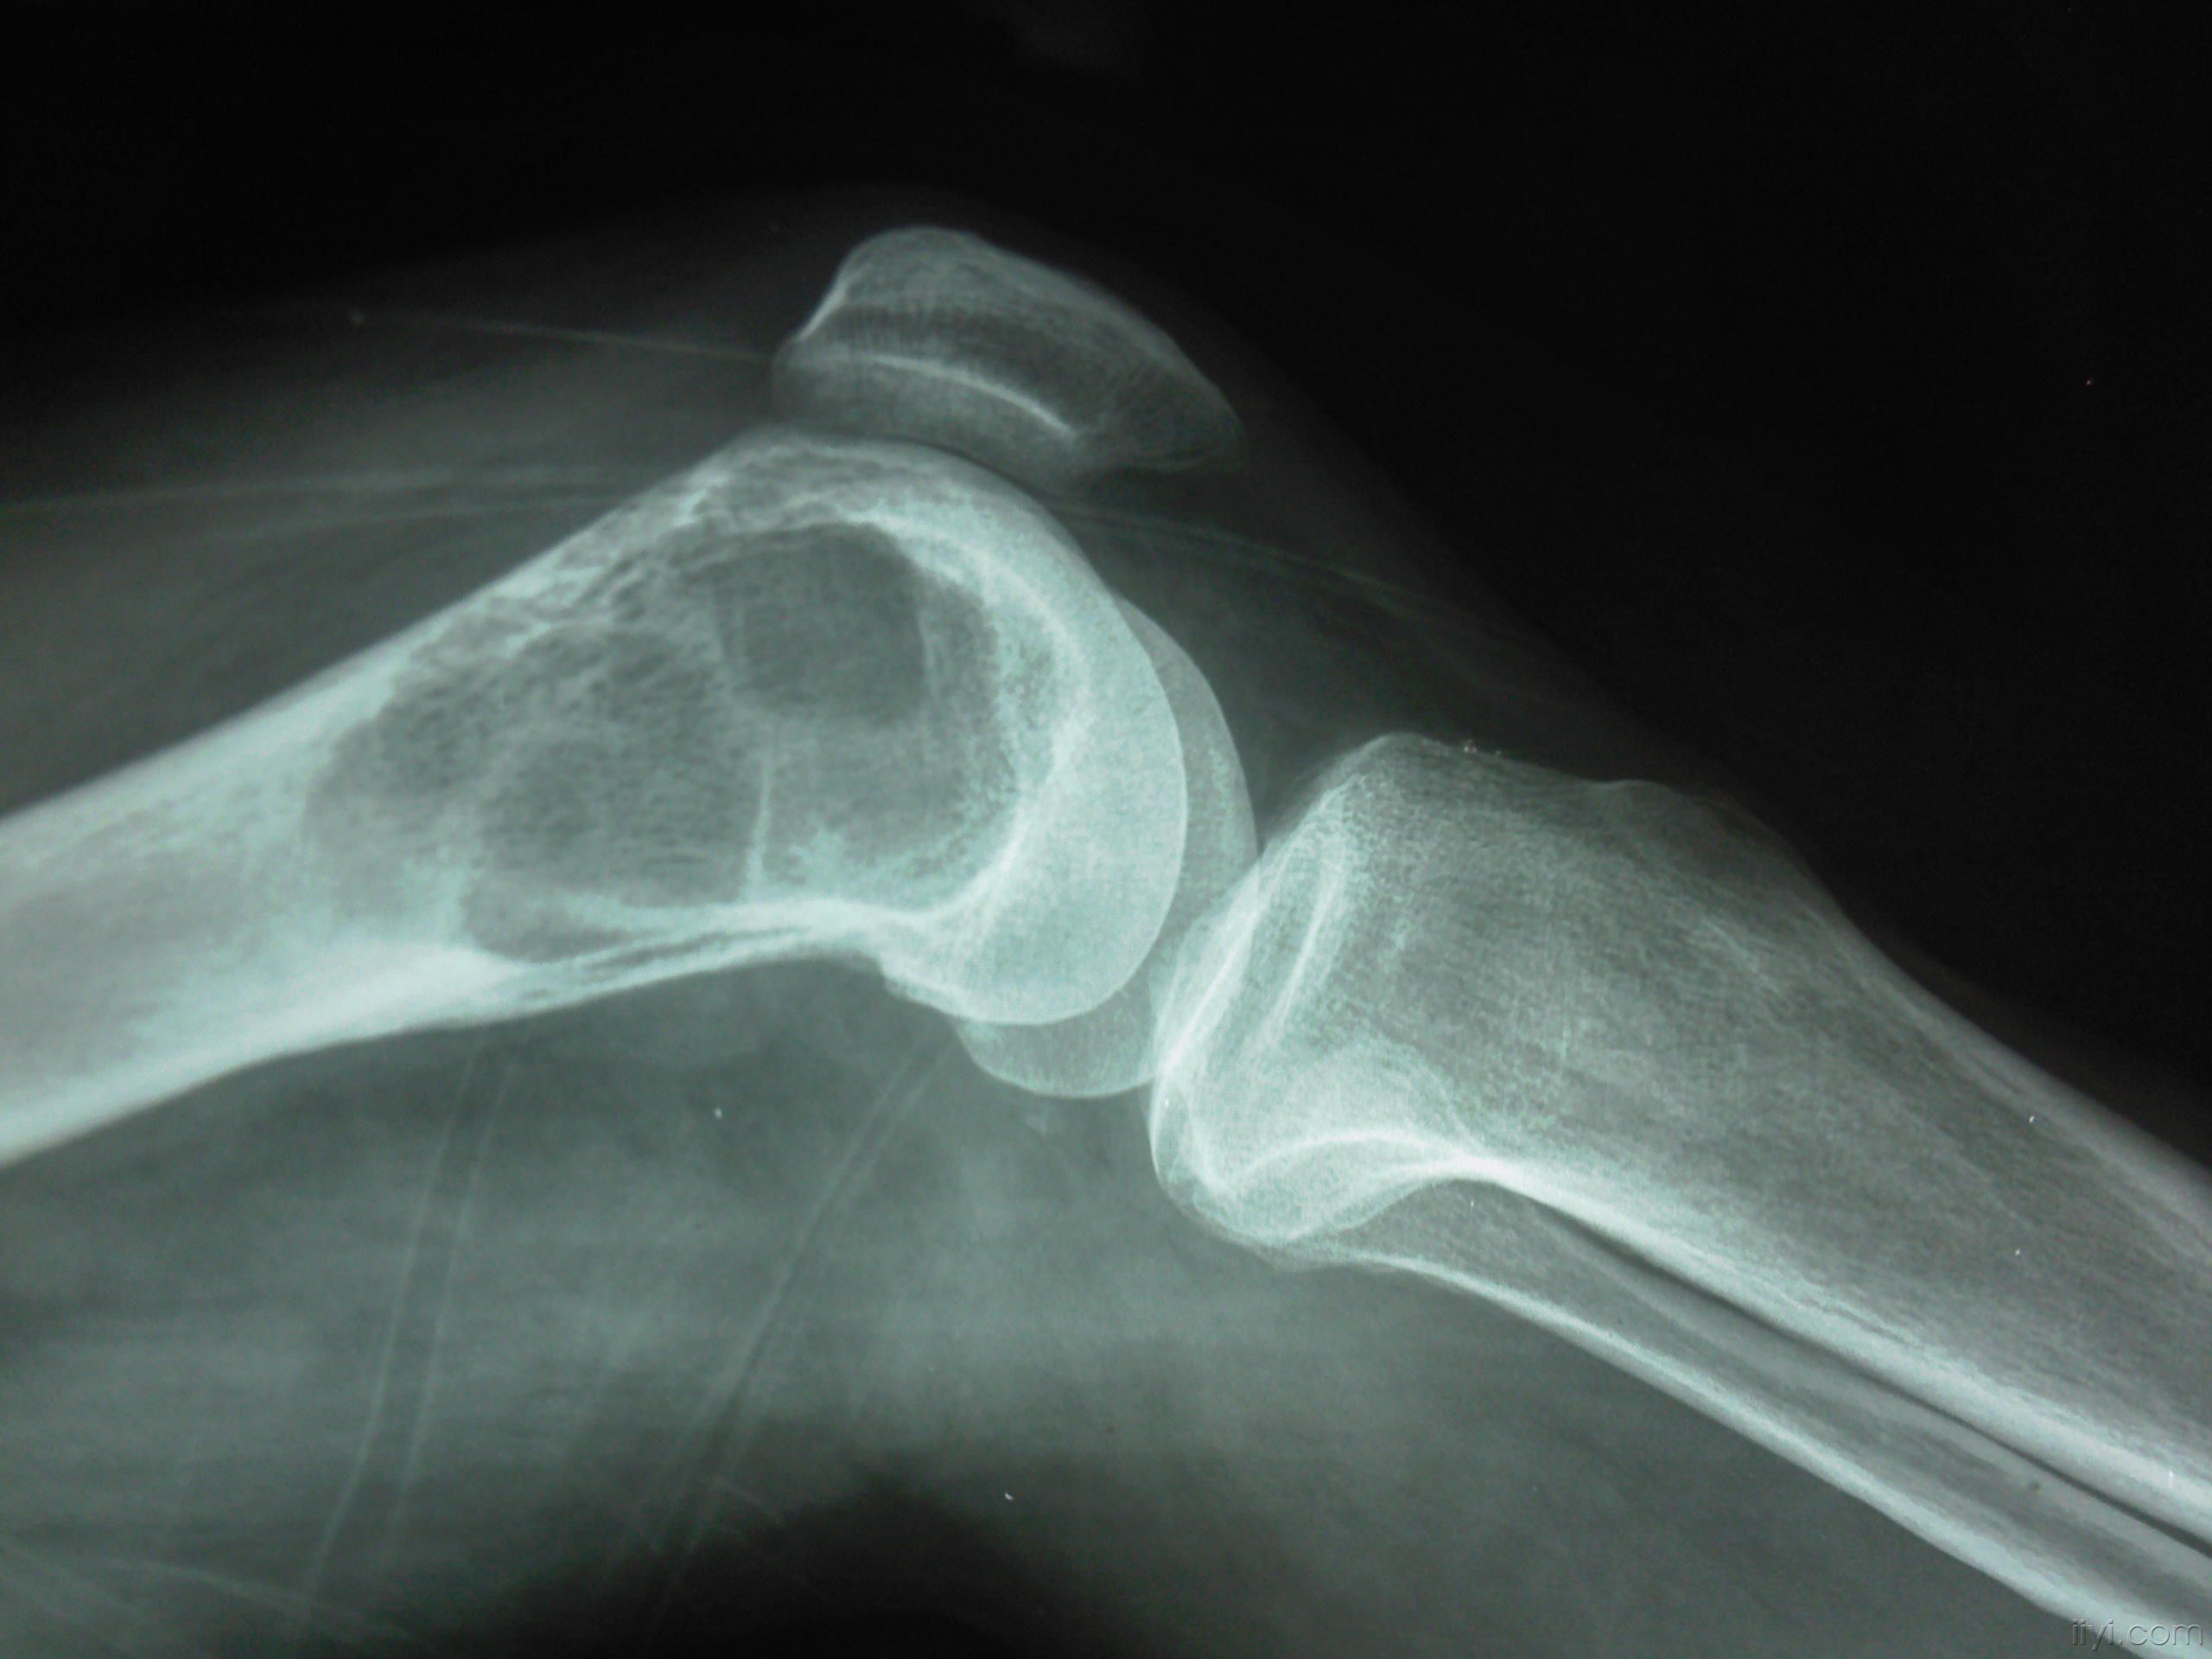

肉眼观,本瘤常侵犯骨骺线已闭合的长骨端,大多数位于骨骺,早期常为偏心性生长,增大的肿瘤使骨皮质受累而向外膨胀。在肿瘤周围往往有菲薄的骨壳,乃由骨内、外膜反应性新生骨构成,肿瘤的境界比较清楚。肿瘤内原有松质骨大部分或全部消失,瘤内常有纤维组织或骨性间隔。由于肿瘤组织的溶骨性破坏,常造成病理性骨折。肿瘤组织呈灰红色,质软而脆,较大的肿瘤常合并出血及坏死,并伴有囊性变而形成大小不等的空腔,囊腔内含有浆液性或血性液体。晚期病例骨性包壳如果被破坏,则可侵犯软组织形成肿块。关节软骨有抗肿瘤浸润的作用,关节软骨下骨间质可完全被破坏,致使关节软骨失去支持而扭曲变形。

骨巨细胞瘤由软而脆且易出血的肉芽样组织所构成,无纤维包囊。由于瘤组织易出血和坏死,故可出现多种多样的病变。因血红蛋白的变化,可使肿,自呈红棕色或绿色。血肿的纤维化可使肿瘤呈灰白色。瘤组织坏死,可使肿瘤呈黄色或形成假囊肿,囊内可能含有胶状或棕色液体,骨质因肿瘤扩张压迫而萎缩,当骨膜下的皮质骨萎缩消失后,骨膜即产生新生骨,在肿瘤进展中新骨消失和再生继续反复,以致在x线照片上皮质骨似乎有被肿瘤由内向外扩张而变薄的错觉。

(一)多发于四肢长骨,其中尤以股骨远端,胫骨近端,桡骨远端及股骨近端为多见。